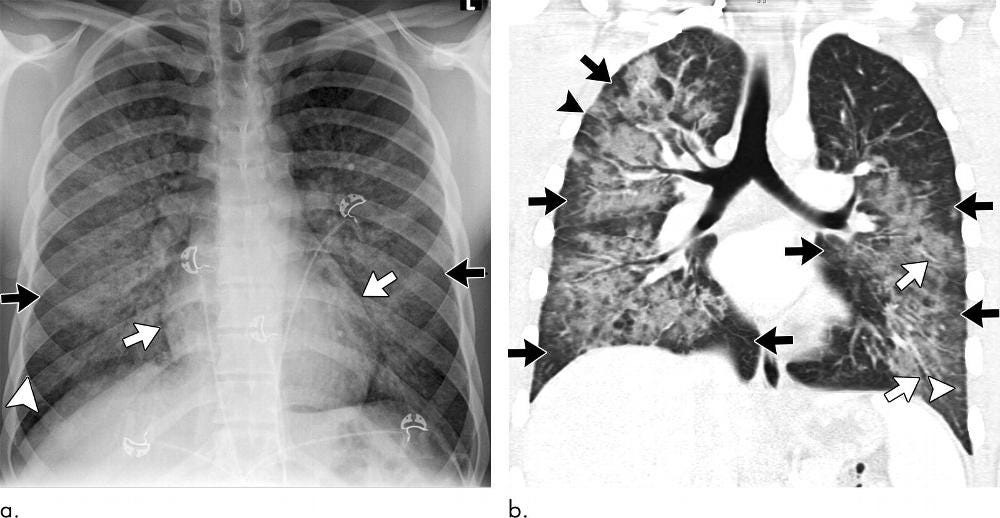

One dramatic real-world example was the 2019 vaping lung injury outbreak known as EVALI (E-Cigarette or Vaping-Associated Lung Injury). Hundreds of young Americans were suddenly hospitalized with what looked exactly like a severe viral pneumonia: cough, chest infiltrates on X-ray, respiratory failure. Doctors scrambled to find a pathogen, even prescribing antivirals and antibiotics[5][6]. But ultimately no virus was found – instead, investigators traced the illness to a chemical toxin: vitamin E acetate contaminating illicit vape cartridges[7]. Once the toxin was identified, it explained everything. Vitamin E acetate in the lungs triggered a severe inflammatory response that perfectly mimicked a viral infection[8]. The “contagion” was an illusion; patients fell ill around the same time simply because they shared the same toxic exposure source, creating a cluster that fooled experts into blaming an infectious outbreak[9][6].